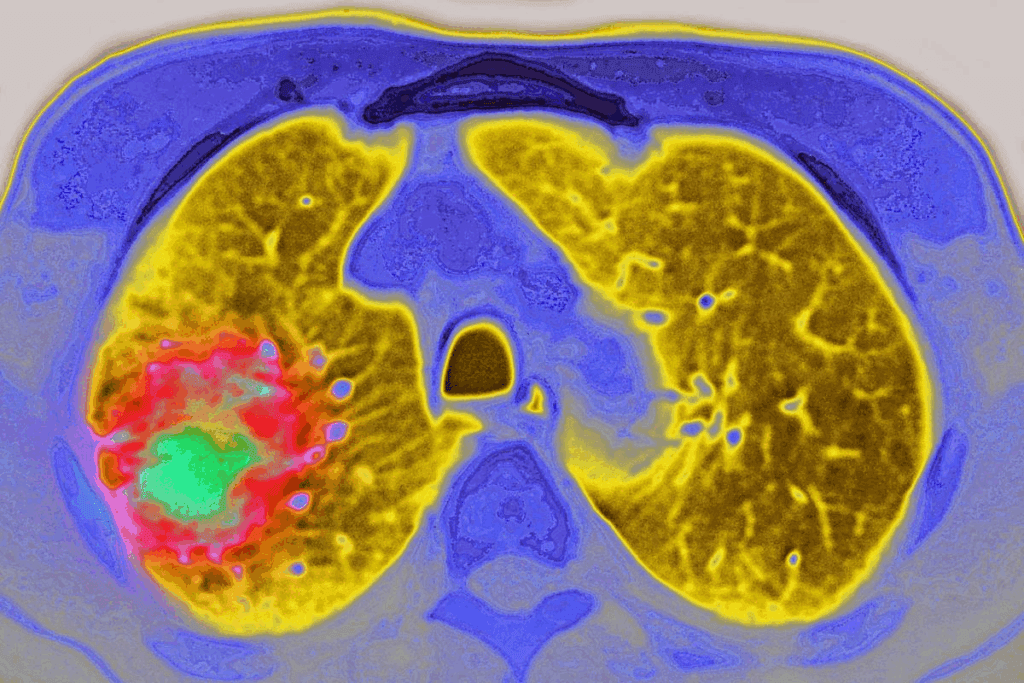

CT-guided biopsy is a new way to get tissue samples for medical tests. It uses CT scans to guide a needle into the right spot. This makes sure the samples are accurate.

A CT scan biopsy, or CT-guided needle biopsy, uses CT scans to guide the needle. It helps get tissue or fluid samples from hard-to-reach places in the body. This is great for diagnosing problems in organs or tissues.

The CT scanner shows real-time images. This helps doctors place the needle exactly where it needs to be.

CT-guided biopsy is used for many health issues. It’s good for checking on lung, liver, kidney, and lymph node problems. It helps find cancers, infections, and inflammatory diseases.

We use real-time CT guidance throughout the procedure. This means we get continuous CT scans. These scans show us where the needle is in relation to the tissue.

This feedback lets us make precise adjustments. It ensures we get the tissue sample from the right spot.